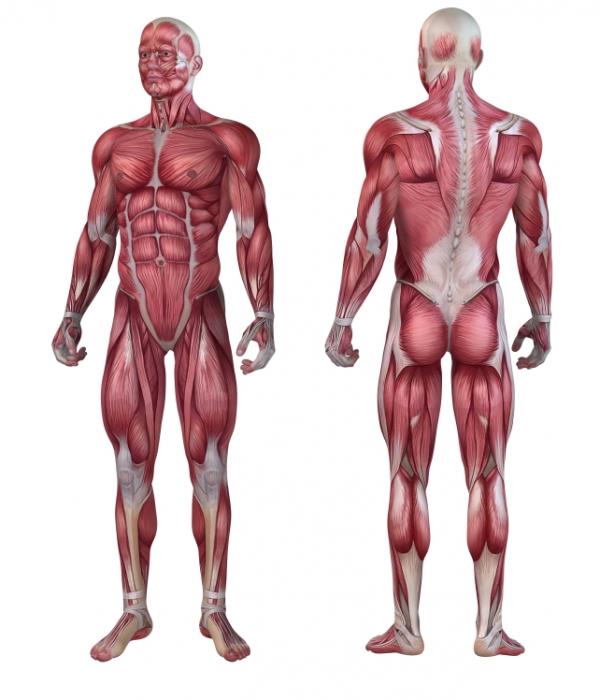

Human anatomy news and research rss tic tac toe tackles alzheimers disease. Human anatomy or anthropotomy is a special field within anatomy.

It studies structures and systems of the human body leaving the study of tissues to histology and cells to cytology. Habits such as napping might influence how humans cope with extreme environments such as those at a polar research facility in winter. Health news posted on december 12 2019 total news research records 239 page 1 of 16 medindia provides you with the latest news and research breakthroughs on human anatomy.

It is a general term that can include human anatomy animal anatomy zootomy and plant anatomy. Anatomy is the branch of biology that is the consideration of the structure of living things. Drawing on multiple scientific disciplines a new team is gearing up for a fresh onslaught on alzheimers.